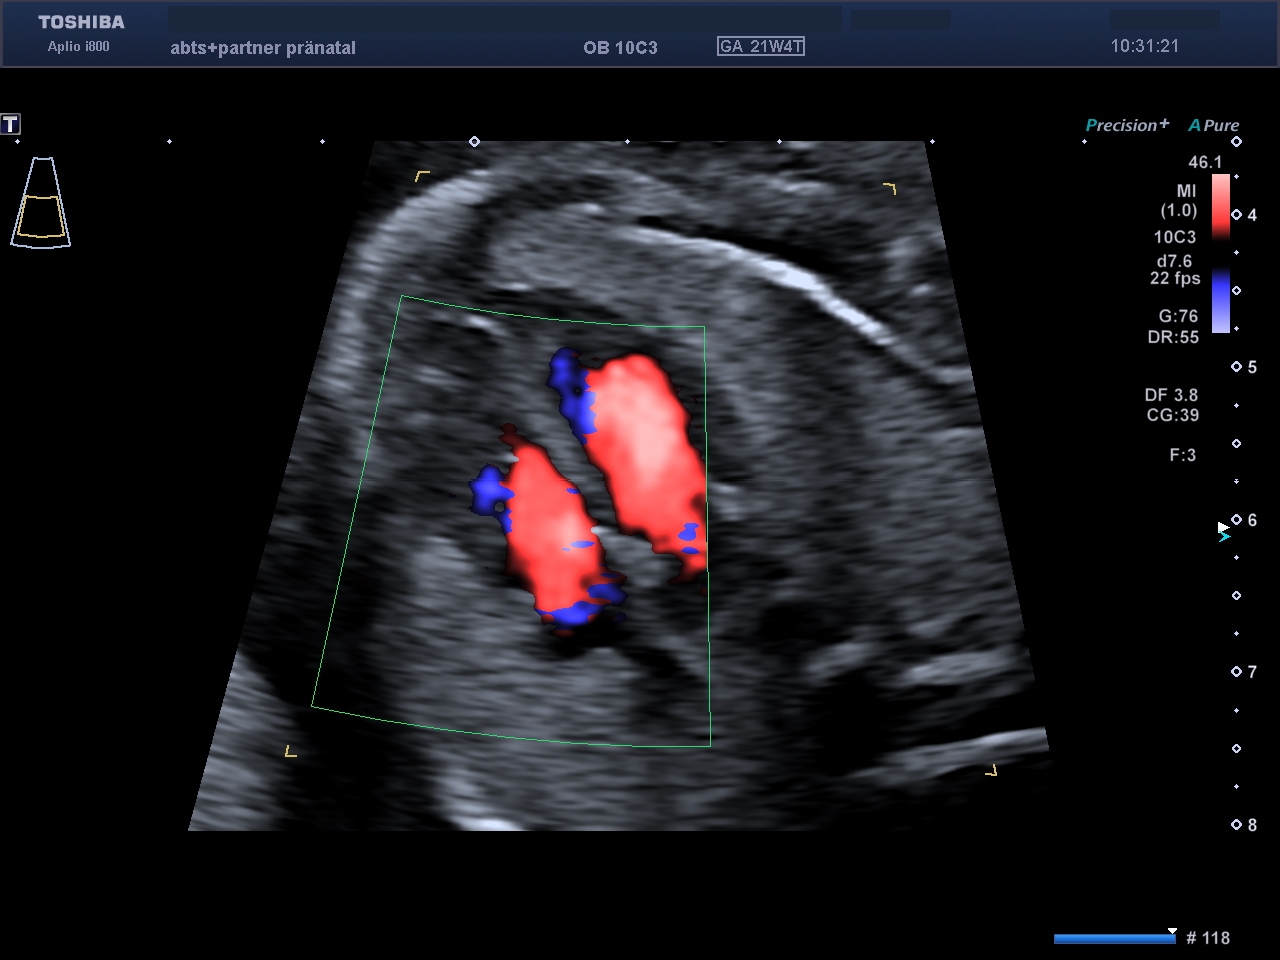

Das kindliche Herz zeigt normale Anatomie und unauffälliges Blutflussmuster.